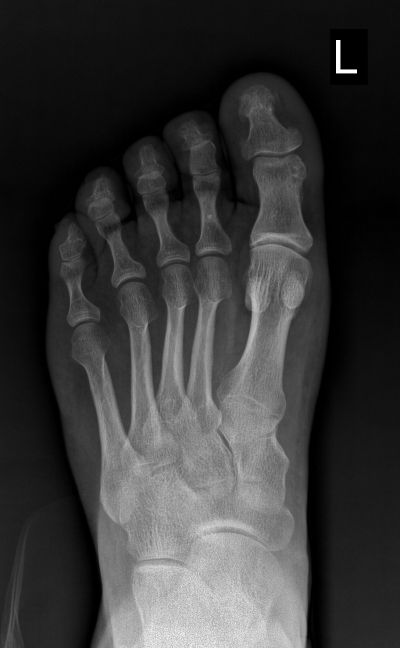

"Болезнь королей" (или подагра)

В рентгенологический кабинет клиники №1 Витерра Беляево поступил пациент - мужчина 1966 г.р., с жалобами на боль при движении (сложность при обувании), покраснения кожных покровов, припухлость мягких тканей в первом пальце левой стопы, травму данного пальца отрицает. Со слов пациента, наблюдается у терапевта по поводу высокого показателя уровня мочевой кислоты в крови (458 мкмоль/л.).

Пациенту выполнена рентгенография левой стопы в 2-х проекциях, при которой выявлено:

В дистальном эпифизе основной фаланги 1-го пальца определяются множественные участки кистовидной перестройки, со склеротическим ободком по переферии - тофусы по типу «пробойников» (депонирование кристаллов мочевой кислоты в костной ткани).

Явления артроза первого плюсне-фалангового и межфалангового суставов.

Заключение:

Рентгенологическая картина подагры-дебют. Р-признаки начального проявления подагрического артрита.

Пациенту рекомендована консультация терапевта, эндокринолога. Рентгенологический контроль.